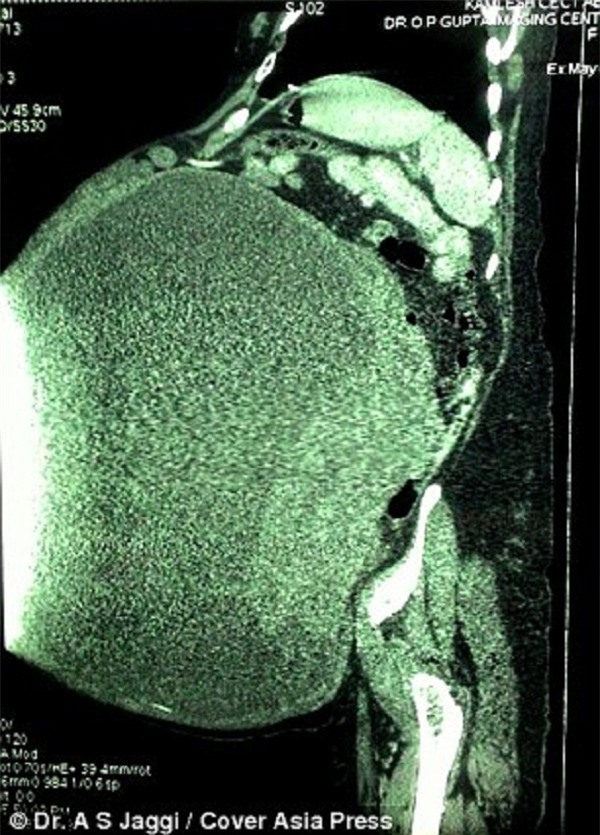

Hình ảnh chụp khối u khổng lồ trong bụng người phụ nữ.

Bác sĩ Jaggi cũng chia sẻ, trong suốt 25 năm trong nghề, ông chưa từng nhìn thấy một khối u kinh khủng như vậy. Các khối u buồng trứng thông thường không có kích cỡ lớn như thế này. Nó dài gần 1 mét và rộng hơn 60 cm. Bệnh viện của ông đã liên hệ với ban tổ chức sách kỷ lục Limca Ấn Độ để ghi danh khối u này.